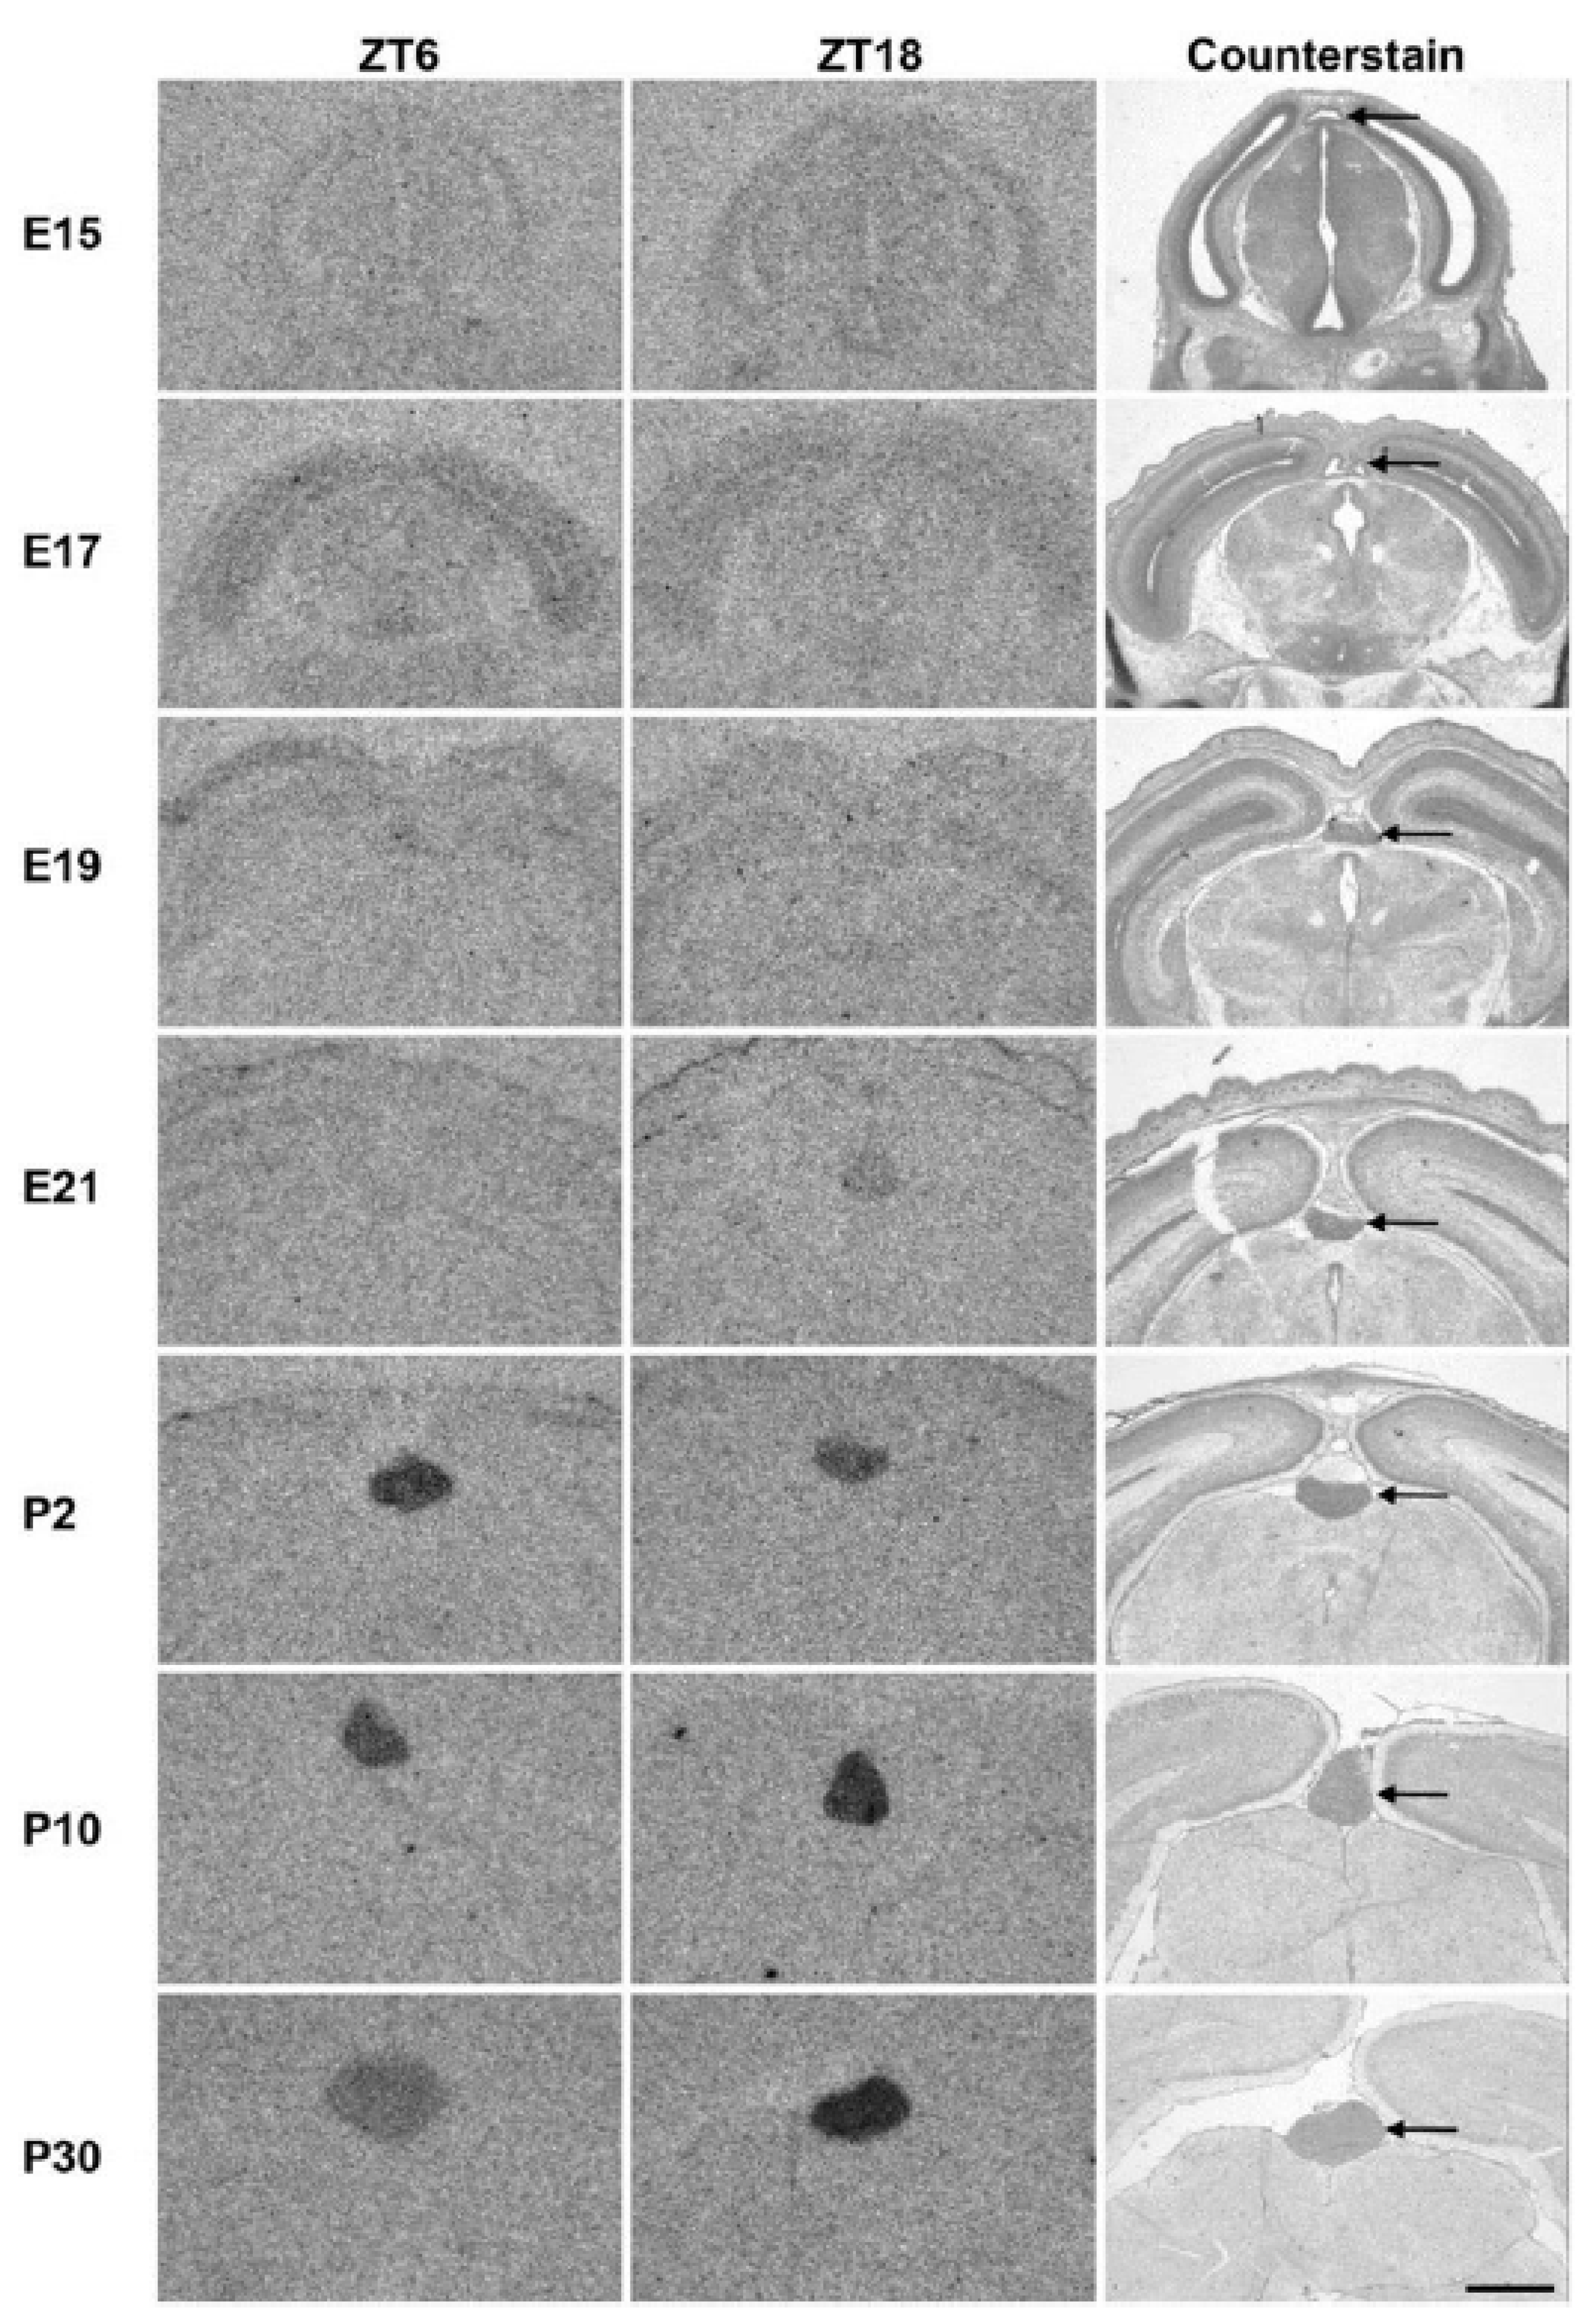

- In 1898, Otto Heubner reported on a 4.5-year-old boy with precocious puberty and tall stature, in whom a pineal tumour was detected at autopsy [180]. This case report drew attention to the endocrinological functions of the pineal gland. The discovery of melatonin by Lerner in 1958/1959 [181,182] marked the beginning of an exponential increase in knowledge about melatonin, which continues to this day.

- In 1924, Ladislaus von Meduna (1896–1964) submitted a fundamental histological study on “the development of the pineal gland in infancy”, in which anatomical preparations of 30 pineal glands from children from the neonatal period to the age of 4 (N = 26) and after the age of 4 (N = 4) were examined [183]. These studies clearly show that the microstructure of the pineal gland develops and differentiates in several phases only within the first year of life, so that its functional capacity is not established until several months after birth.